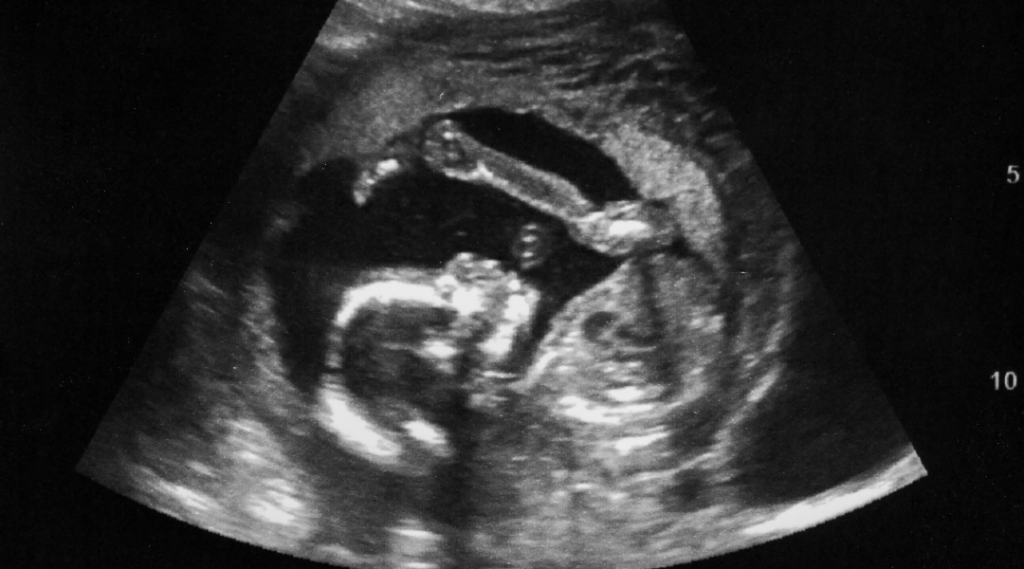

SEO betekent structureel echoscopisch onderzoek. Verloskundige Praktijk YuuX in Wijchen biedt een medische echo aan bij 13 en 20 weken in het Verloskundig Centrum Nijmegen. Deze echo’s zijn onderzoeken naar lichamelijke afwijkingen bij je kindje. Ze zijn niet verplicht. We vertellen je erover tijdens de eerste afspraak waarna je mag kiezen of je wel of geen medische echo wenst. Mocht je hiervoor kiezen regelen we tijdens je tweede afspraak de verwijzing. Zowel de uitleg over deze onderzoeken als de echo’s zelf en eventueel vervolgonderzoek worden vergoed.

Het doel van deze echo’s is dus het opsporen van lichamelijk afwijkingen. Het kindje wordt van top tot teen bekeken met de echo. Een lichamelijke afwijking betekent dat een deel van het lichaam van het kind er anders uitziet dan normaal. Voorbeelden hiervan zijn een open ruggetje, open schedel, hartafwijkingen, gat in het middenrif of de buikwand of nierafwijkingen. Daarnaast wordt de groei gemeten, het vruchtwater en de ligging van de placenta beoordeeld. Als er geen bijzonderheden worden gezien mag je daarop vertrouwen maar is het belangrijk om te weten dat je nooit 100% zekerheid krijgt omdat niet alles zichtbaar is met de echo. In principe worden syndromen niet gezien met de echo’s. Bij 5 van de 100 zwangeren zijn er aanwijzingen voor lichamelijke afwijkingen en bij 95 dus niet. Mocht er een verdenking zijn op een lichamelijke afwijking dan krijg je een verwijzing naar de afdeling Prenatale Diagnostiek in het Radboudumc. Als de afwijking wordt bevestigd krijg je daar verdere uitleg over de afwijking, de mogelijke gevolgen en behandelopties.

De 13 wekenecho

De 20 wekenecho